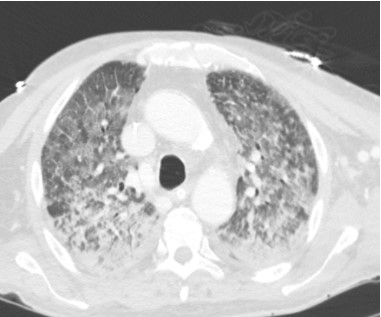

Se le realizó videocolonoscopia que evidenció mucosa eritematosa y congestiva, sin sangrado activo. Al noveno día de internación, el paciente desarrolló disnea, taquipnea, deterioro de la mecánica ventilatoria, tos seca y hemoptisis, con desaturación en aire ambiente. La PCR multiplex para virus respiratorios resultó positiva para SARS-CoV-2, rinovirus y enterovirus. La tomografía de tórax mostró infiltrado bilateral difuso de patrón reticulonodulillar (Fig. 1), y el lavado broncoalveolar (BAL) evidenció débito hemático, interpretándose el cuadro como hemorragia alveolar difusa de probable origen infeccioso. Se instauró tratamiento con antibióticos de amplio espectro, remdesivir, corticosteroides en dosis altas, nebulizaciones con ácido tranexámico y soporte ventilatorio con cánula de alto flujo. A pesar de estas medidas, evoluciona desfavorablemente, requiriendo intubación orotraqueal y ventilación mecánica al día 11 de internación.

Figura 1. Tomografía de tórax corte axial. Texto alternativo para asistencia visual: tomografía de tórax corte axial por encima de bifurcación de la carina y por debajo del cayado aórtico; se puede observar en ventana de parénquima pulmonar un patrón reticulonodulillar bilateral con predominio de zona posterior y central.